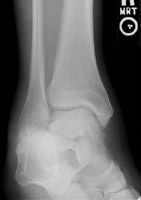

- Click on the image for a larger versionAAP radiograph of the ankle. This shows a comminuted minimally displaced fracture of the distal fibula, Weber A in classification.

Weber A fractures consist of fibular fractures distal to the level of the tibiotalar joint. These fractures are generally treated nonoperatively. The syndesmosis between the tibia and fibula remains intact. The fracture results from supination-adduction injuries. The medial malleolus may be fractured or the deltoid ligament may be disrupted.